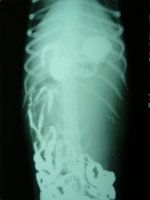

腹背正位平片图1 侧位平片 图2

图1可以看到,在胃的后侧有一密度均匀的巨大灰色软组织阴影的影像占位,前方与其它组织器官无明显界限,左方紧贴腹壁且界限不清,后方越过第四腰椎,右方侵袭到腰椎右侧,将原有的肠管压迫到腹后侧。

图2看到,在L1-L5的下方有一密度均匀的巨大灰色软组织阴影的影像,该影像前方和上方边界不清,后方与下方界限较清楚,从外型和位置来看此影像极有可能是肾脏。